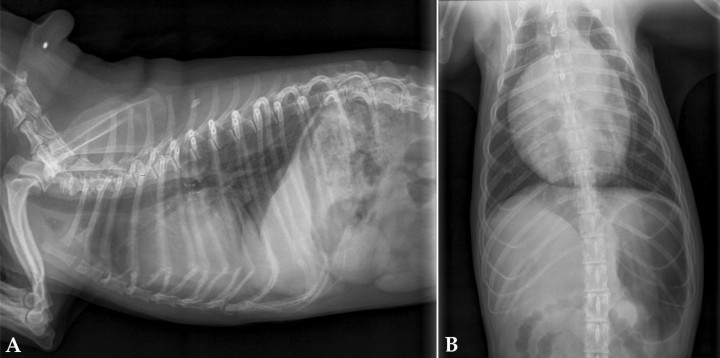

- Aumento de tamaño de la aurícula izquierda (Fig. 2). La aurícula izquierda se sitúa ventral al bronquio principal izquierdo. En el aumento de tamaño de la aurícula izquierda observaremos una desviación dorsal del bronquio en la proyección lateral. En la imagen ventrodorsal veremos un aumento de separación entre los bronquios principales y una desviación hacia las dos de la orejuela izquierda.[ García MI: Atlas de interpretación radiográfica en pequeños animales. Zaragoza: Ed Servet; 2014. ]

<p>Radiografías de la cavidad torácica de un paciente con un tumor en la aurícula izquierda. (<strong>A</strong>) Lateral. (<strong>B</strong>) Ventrodorsal.</p>

Radiografías de la cavidad torácica de un paciente con un tumor en la aurícula izquierda. (A) Lateral. (B) Ventrodorsal.

- Aumento de tamaño de la aurícula derecha (Fig. 3): produce un desplazamiento dorsal de la tráquea craneal a la carina sin afectar a esta en la proyección lateral.

<p>Radiografías de la cavidad torácica de un paciente con un tumor en la aurícula derecha. (<strong>A</strong>) Lateral. (<strong>B</strong>) Ventrodorsal.</p>

Radiografías de la cavidad torácica de un paciente con un tumor en la aurícula derecha. (A) Lateral. (B) Ventrodorsal.

- Derrame pericárdico (Fig. 4): produce una imagen globosa del corazón con desplazamiento dorsal de la tráquea e hipoperfusión pulmonar.

<p>Radiografías de la cavidad torácica de un paciente con derrame pericárdico. (<strong>A</strong>) Lateral. (<strong>B</strong>) Ventrodorsal.</p>

Radiografías de la cavidad torácica de un paciente con derrame pericárdico. (A) Lateral. (B) Ventrodorsal.